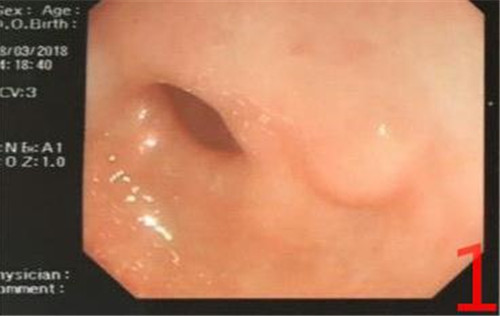

临床信息:患者男,54岁,因腹胀、纳差2月余来我院消化内科就诊。行胃镜检查,于胃窦后壁见一丘状隆起,大小为0.9×0.7cm(图1),行ESD术并送病检。